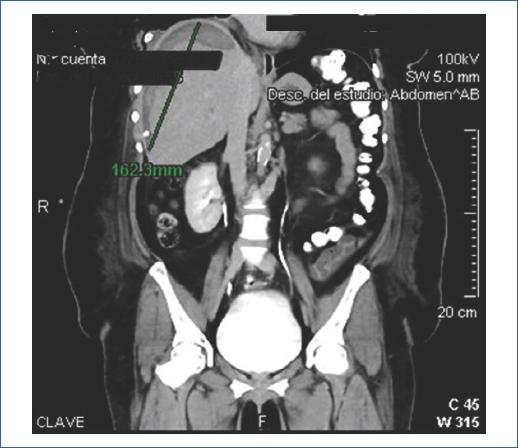

Paciente de sexo femenino de 47 años, sin antecedentes relevantes. Con diagnóstico por ultrasonido de coledocolitiasis, se realizó CPRE programada. Procedimiento a cargo del médico adscrito, asistido por residente; tiempo de canulación: 3 minutos, con dos intentos. Se realizó esfinterotomía, identificación de defecto de llenado, barrido con balón y colocación de endoprótesis biliar. Posteriormente presentó dolor epigástrico intenso. Laboratorios: Hb 8.1, BT 2.16, BD 0.12, BI 2.04; AST 110, ALT 45, FA 115, GGT 95, DHL 126, amilasa 86, lipasa 67. La TC reveló hematoma subcapsular hepático de 1,250 ml (Fig. 4). Se colocó drenaje percutáneo, con gasto inicial de 900 ml y gasto diario de 50 ml. Egresó a los 13 días, con resolución clínica y programación para colecistectomía laparoscópica.